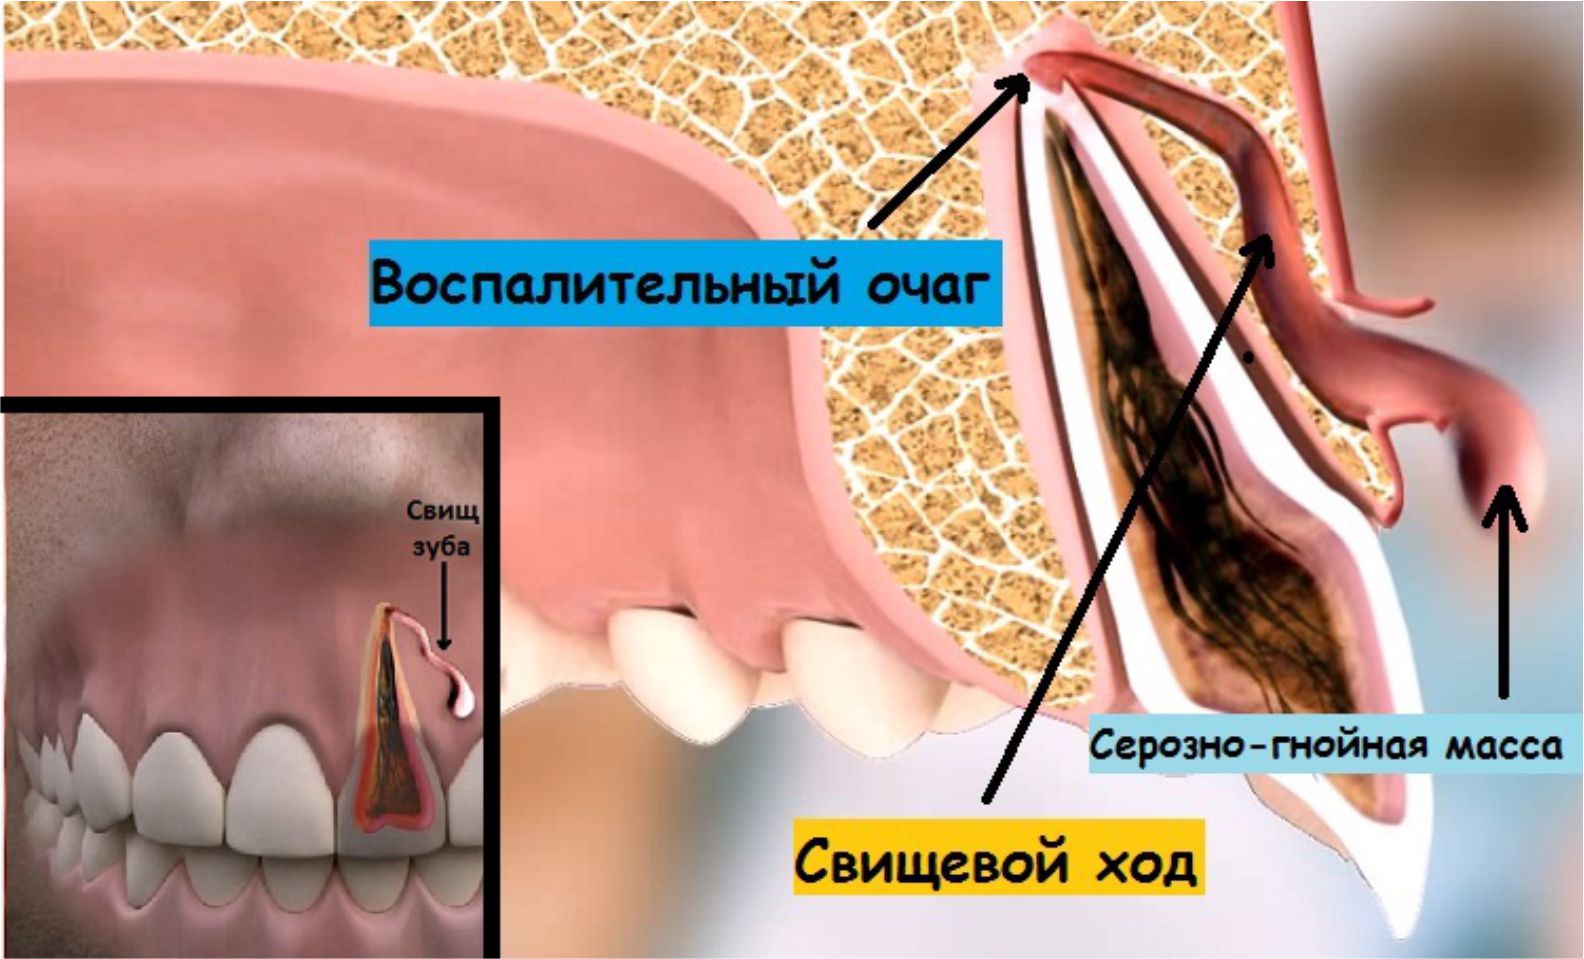

Реплантация зуба: Этапы и особенности операции